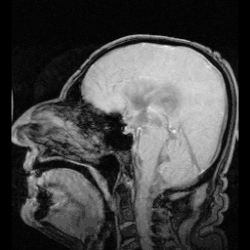

MRI die de circulatie van hersenvocht toont.

De aanmaak van hersenvocht vindt plaats door filtratie van bloed in de plexus choroideus. Deze ligt onder andere in de zijventrikels. Vanaf hier stroomt het via het foramen van Monro naar de derde ventrikel, om vervolgens via het aquaduct van Sylvius in de vierde ventrikel en het centrale kanaal terecht te komen. Vanuit hier stroomt het door het foramen van Luschka en het foramen van Magendie. Dan komt de vloeistof in de ruimte tussen het spinnenwebvlies en het zachte hersenvlies, de subarachnoïdale ruimte. Het hersenvocht komt uiteindelijk boven in de schedel terecht, in de sinus sagittalis superior, waar het door cellen wordt opgenomen. Deze cellen worden de granulationes arachnoideae of granula meningica[3] genoemd. Na opname wordt het vocht weer door het bloed opgenomen.